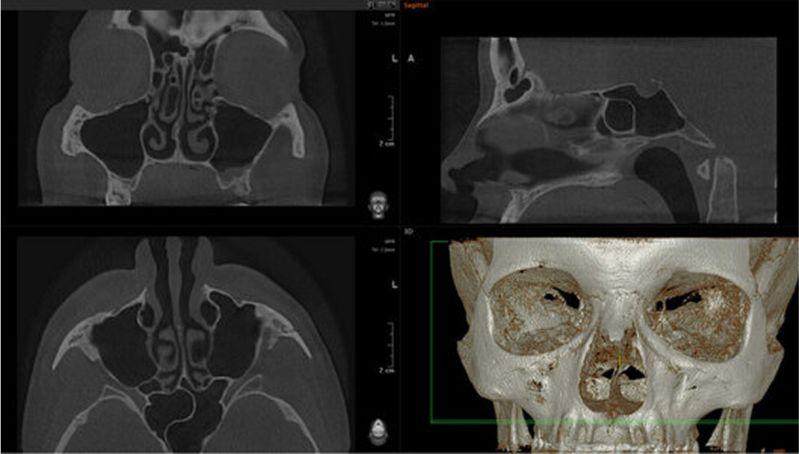

Диагностика околоносовых пазух

КЛКТ придаточных пазух позволяет визуализировать верхнечелюстные, лобные, клиновидные пазухи и решетчатые лабиринты, а также детально оценить состояние зубов верхней челюсти как потенциального источника патологии.